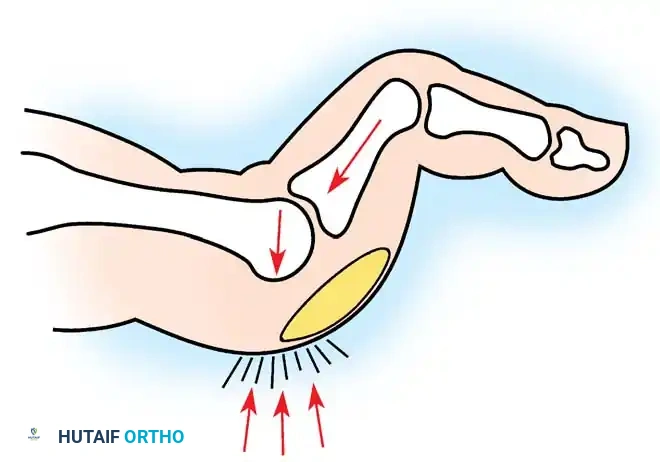

Gradually, this concentrated extension force completely dislocates the MTP joints. At end-stage disease, the proximal phalanx rests entirely on the dorsal aspect of the metatarsal neck.

- Distal Migration of the Plantar Fat Pad: As the proximal phalanx dislocates dorsally, it drags the plantar aponeurosis and the protective plantar fat pad distally.

- Intractable Plantar Keratoses (IPKs): The metatarsal heads are left completely uncovered and prominent against the plantar skin, leading to painful callosities and a high risk of skin ulceration.

- Osteotomy: An oscillating saw is used to resect the metatarsal heads at the anatomical neck. It is imperative to create a smooth, parabolic cascade (the 2nd metatarsal should be the longest, tapering down to the 5th).

- Soft Tissue Balancing: The plantar plate and fat pad, which have migrated distally, are mobilized and pulled proximally under the remaining metatarsal stumps. If the toes remain contracted, closed osteoclasis or PIP joint resection arthroplasties may be performed.

Fig. 81-9 (A, B) Radiographic evidence of bony proliferation at the distal end of the resected metatarsals. This remodeling can lead to recurrent plantar pressure and necessitates adequate initial resection.

Common long-term objective recurrences include:

3. Bony proliferation (osteophyte formation) on the distal ends of the resected metatarsals, leading to recurrent plantar keratoses.